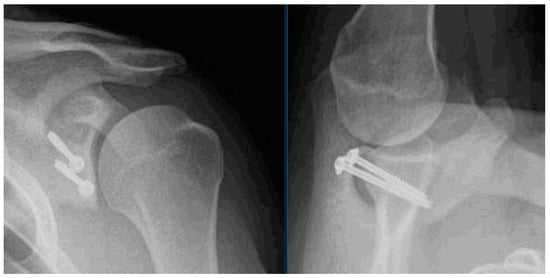

After surgery, the patient is placed in a simple sling for approximately two weeks. Post-operative radiographs are obtained at the first post-operative visit to ensure proper graft and hardware positioning (Figure 6). Physical therapy is initiated after the first post-operative visit, with a focus on gentle passive and active–assisted range-of-motion exercises. Internal rotation and adduction should be avoided to minimize the early loading of the bone graft. We prefer an aquatic therapy exercise regimen if possible. Active strengthening is initiated at twelve weeks, and return to sport is typically permitted at 4 to 6 months post-operatively.

Figure 6.

Grashey and axillary radiographs are obtained post-operatively. The XRs shown demonstrate appropriate position of the graft, flush with the native glenoid rim.